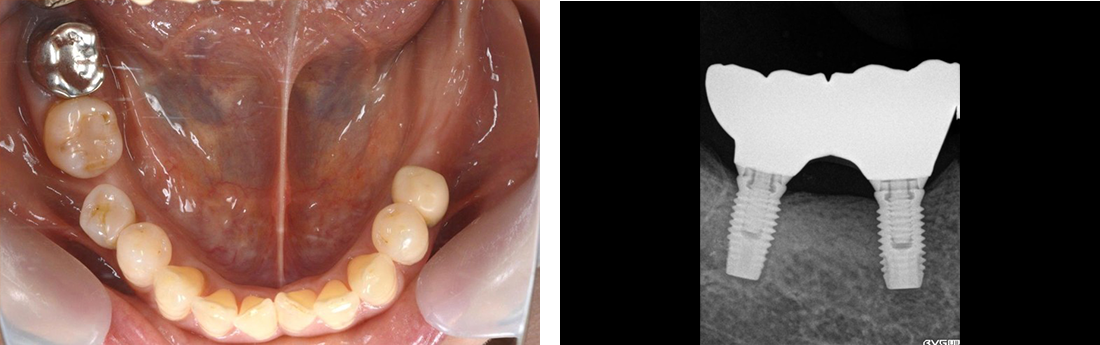

インプラント症例 Case1

Treatment cases

Before

After